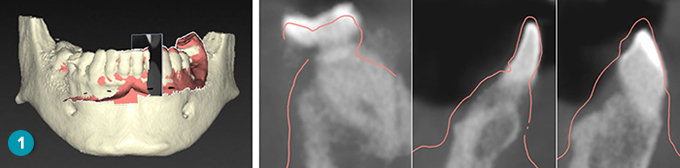

On the Check result page of the wizard, verify whether the automatic alignment is correct by scrolling through the reslices. The outline of the aligned dental scan (default pink color) must accurately correspond to the occlusal information of the teeth within the (CB)CT scan. It is the clinician’s responsibility to make sure this step is correct.

Warning Improper alignment of the CBCT scan and the surface scan will result in an incorrect surgical template and may not be used for surgery. |